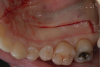

The graft was placed to the height of the original free gingival margin (FGM) (Figure 5), and no attempt was made to cover what had been the exposed root areas—the only areas covered were where biologic attachment had been previously. Interproximal sutures were used to hold the FGG in place, and a surgical dressing was applied. Figure 6 shows successful 13-year results.

Fig 5. The graft was placed on the roots to the level of the presurgical FGM and completely replacing the native tissue (marginal graft placement).

Fig 6. View of 13-year result confirming no increase in recession, maintenance of an ample band of attached gingiva, and success in preventing worsening recession over time.